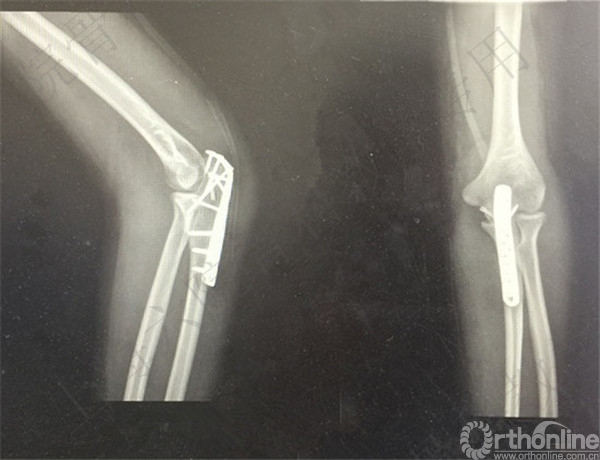

患者左尺骨鹰嘴骨折,取出内固定。

术后X线摄片示:左尺骨鹰嘴内固定取出,空心钉留置。

医方在术前未充分告知患者存在内固定取出困难、断钉、留置内固定、术中骨折和术后在骨折等风险。医方存在告知缺陷等过失。